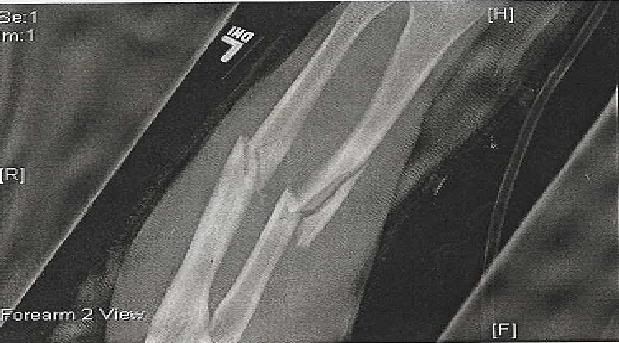

I was in a motorcycle accident 15 months ago.

Injuries:

Compound fracture of my femur - bone shot through my leather suit, split the knuckle on the femur in the knee in half

Shattered my forearm/humerus

Ripped my arm off of my body and was held on by the skin only - all nerves were severed, rendering the arm useless

Tore the brachial artery into my arm - required 16bags of blood (2 full transfusions) over 12 hrs. - died of blood loss and had to be revived

Cracked scapula

Fractured 4 vertebrae

Collapsed lung

Concussion

http://i12.photobucket.com/albums/a219/jdoggg1/forearm.jpg